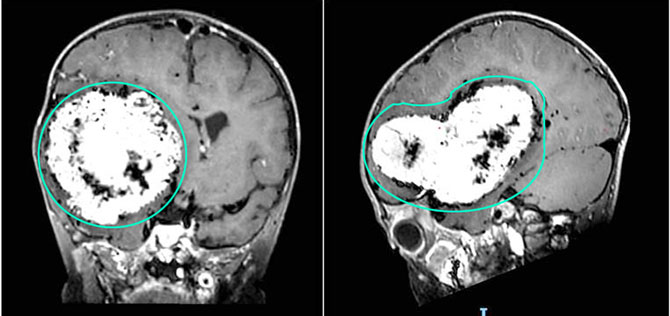

“经头部MR增强检查发现,孩子右侧大脑半球存在一巨大颅内占位,肿瘤直径约10cm,占据三分之一至四分之一的大脑空间。”省医神经外科主任医师周东意识到,这严重压迫周围正常脑组织,病情十分危急,需尽快手术切除。

在团队的通力合作下,肿瘤被完整切除,切除组织大小约13×7×4厘米,家长悬着的心终于落地。术后天天恢复良好,意识状态逐渐改善,可自主进食,右侧肢体肌力逐步恢复。术后一周,天天便能在搀扶下站立,且未出现新发神经功能障碍。

切除巨大肿瘤后,会影响孩子后期的大脑发育吗?“复查头部MR显示肿瘤全切,周围脑组织受压解除,脑中线结构复位。”周东解释称,天天的肿瘤属于脑膜瘤,脑膜瘤是长在脑组织外面的独立肿瘤,非浸润性生长。因此,肿瘤切除后,脑组织会很快恢复弹性,填充到肿瘤缺失的部位,反而对大脑功能起到恢复和促进作用。